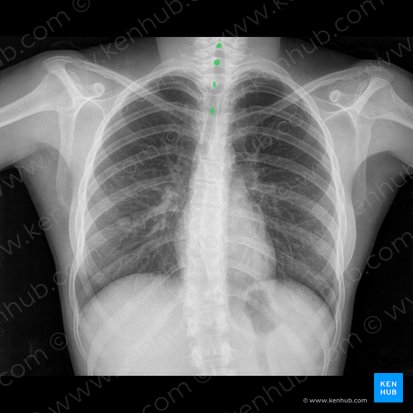

Rotation

Um zu beurteilen, ob Patient:innen in gerader Position, also nicht mit dem Oberkörper zum Detektor verdreht (rotiert) geröntgt wurden, sollten die medialen Enden der Schlüsselbeine in einer Ebene mit den Dornfortsätzen der Wirbelsäule auf der Aufnahme zu erkennen sein. Außerdem sollten die Abstände zwischen den medialen Enden des linken und rechten Schlüsselbeins und der Dornfortsätze möglichst gleich sein.

War der Oberkörper bei der Röntgenaufnahme nach rechts rotiert, so wird der Abstand zwischen dem medialen Ende des rechten Schlüsselbeins und den Dornfortsätzen größer dargestellt, als der Abstand zwischen dem medialen Ende des linken Schlüsselbeins und den Dornfortsätzen. War der Oberkörper links verdreht, so verhält es sich umgekehrt: Der Abstand zwischen dem linken Schlüsselbein und den Dornfortsätzen wird vegrößert dargestellt.